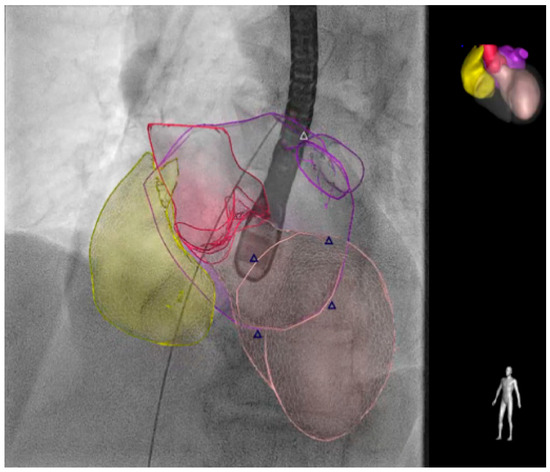

When alternatives are unavailable, fusion imaging (Figure 3) and transthoracic echocardiography may be used as an alternative to traditional TEE [65,66].

Figure 3.

The EchoNavigator® (Philips Medical System, Andover, MA, USA) live image guidance. The smart fusion technology simplifies visualization by fusing real-time X-rays and live echo. EchoNavigator may give interventionalists a supportive anatomical understanding and smooth guidance during structural heart disease interventions to reduce the time undergoing TEE. The different colors distinguish various cardiac structures, with the triangles indicating the position of the mitral valve. The right atrium is shown in yellow, the aorta in magenta, the left ventricle in pink, and the left atrium in purple as indicated in the cartoon in the top right. TEE: transesophageal echocardiography.